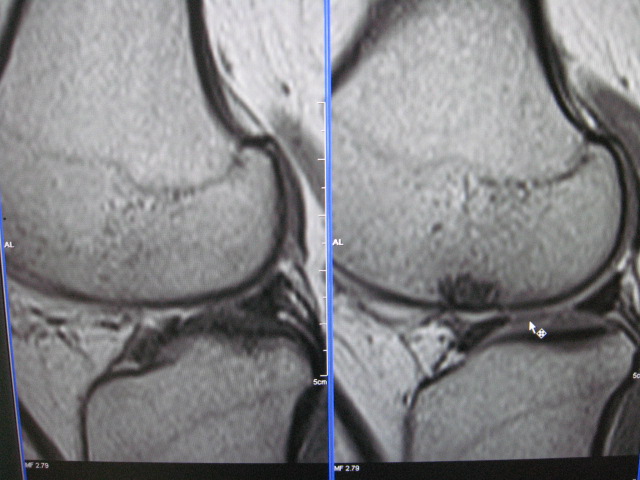

以下是引用克山在2007-10-21 9:57:00的发言:[br]符合股骨外侧髁剥脱性骨软骨炎。创伤是其主要原因,病理上为软骨下骨质局限性缺血性坏死,好发股骨内外侧髁,mr表现为软骨下局限性长t1长t2信号,有时t2像周围可见条状高信号。

以下是引用453506471在2007-10-19 22:23:00的发言:[br]剥脱性骨软骨炎